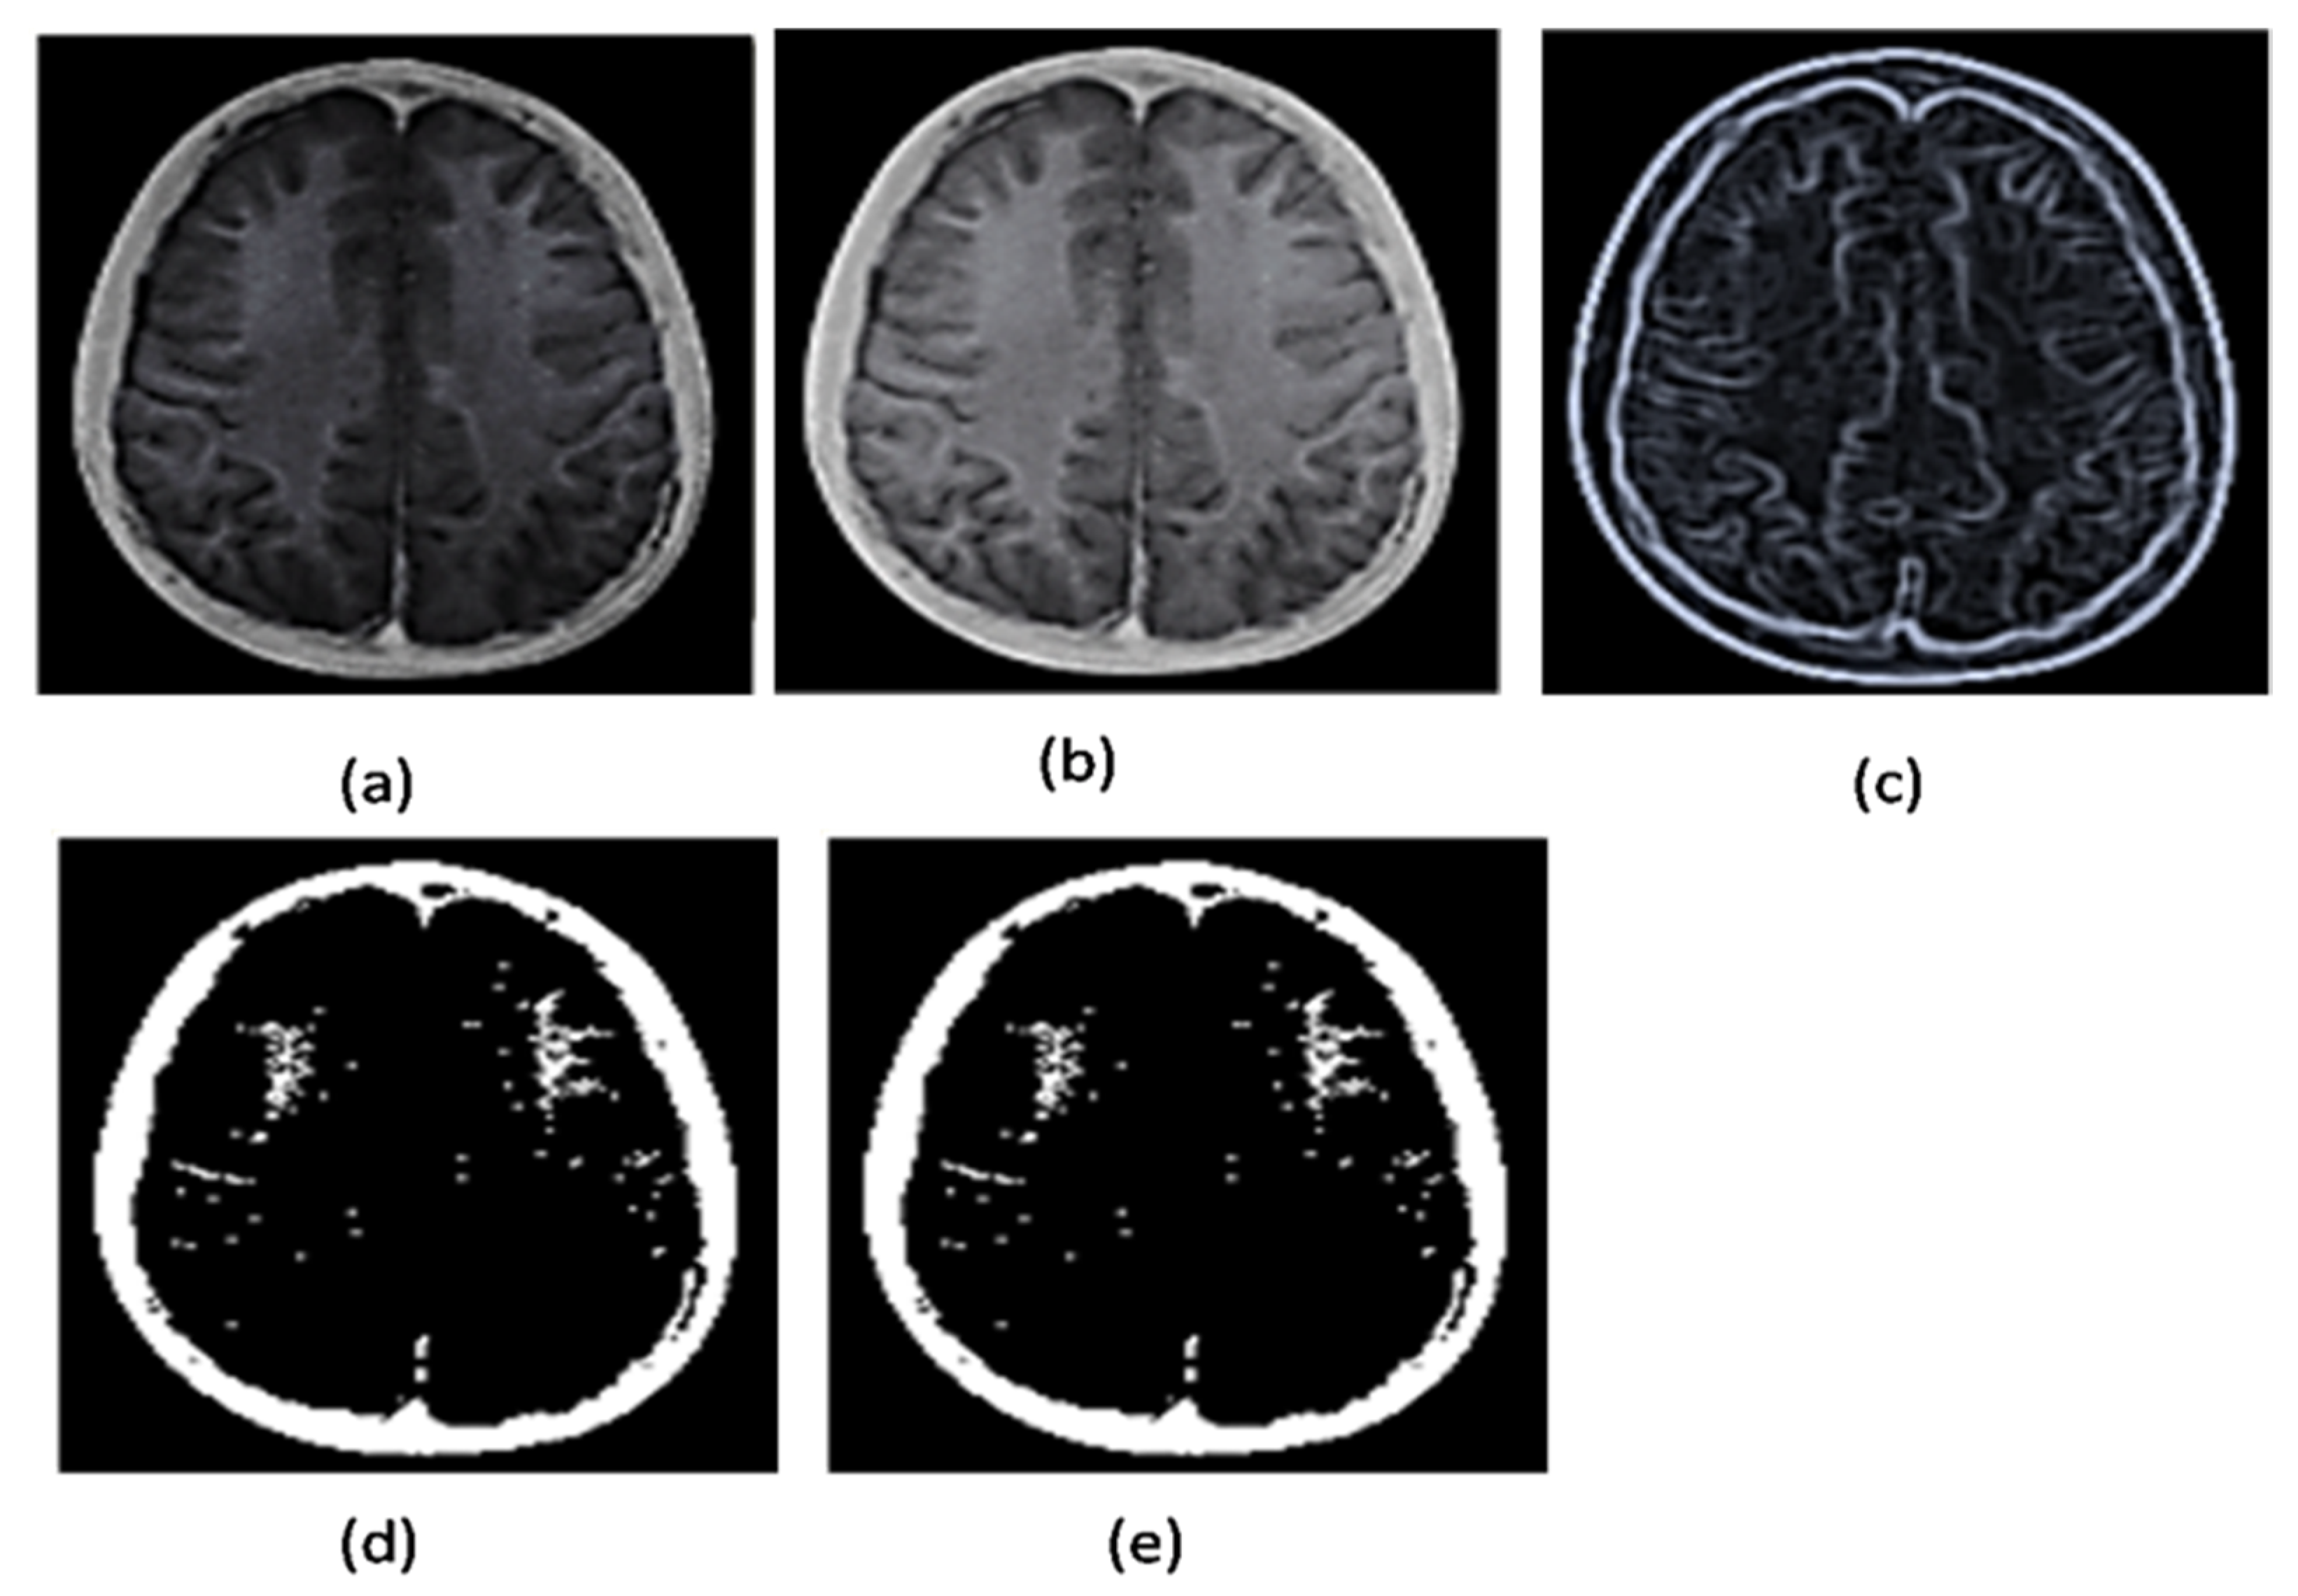

2.2.3. Noise Removal

2.2.4. Grayscale Conversion

2.2.5. Image Enhancement

2.2.6. Image Binarization

2.2.7. Area Segmentation using Watershed Algorithm